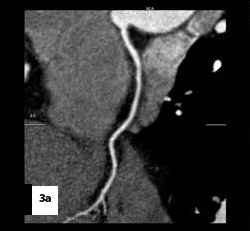

Five patients (12.5 %) had normal angiograms [Table/Fig-2,2b,3,3b], six (15%) had non-significant disease [Table/Fig-4,4b,5a,5b] and 29 patients (72.5%, 26 male & 3 female) had significant disease [Table/Fig-6a,6b],[7a,7band8] on CT coronary angiography, which was also proved on invasive angiography [Table/Fig-9]. The incidence of significant coronary detected was highest in age group of 41-60 years [Table/Fig-10].

Curved reformatted image,

Catheter angiography image showing non-significant stenosis in mid RCA